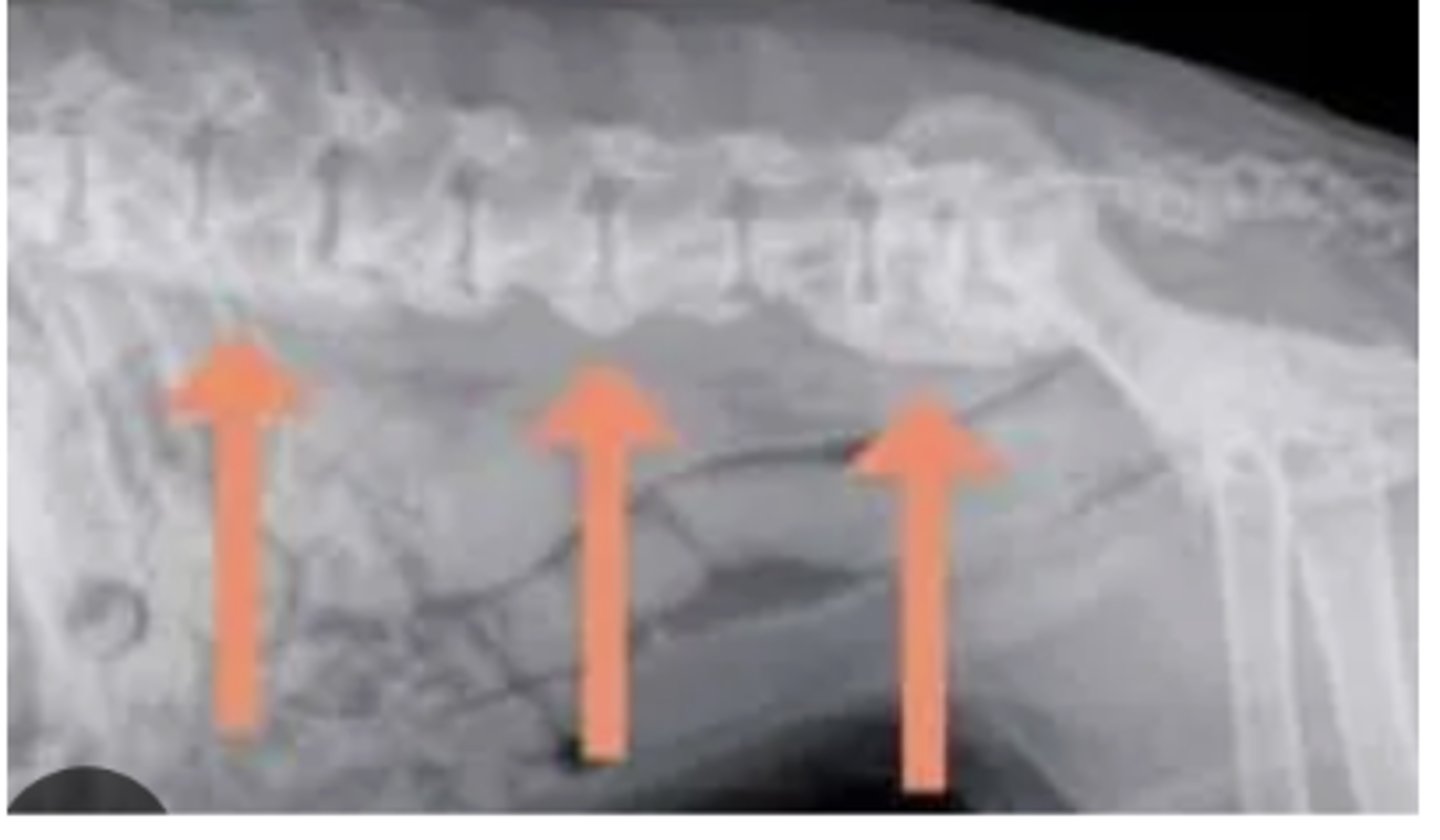

Spondylosis deformans

What abnormality is shown in this radiograph of the spine?